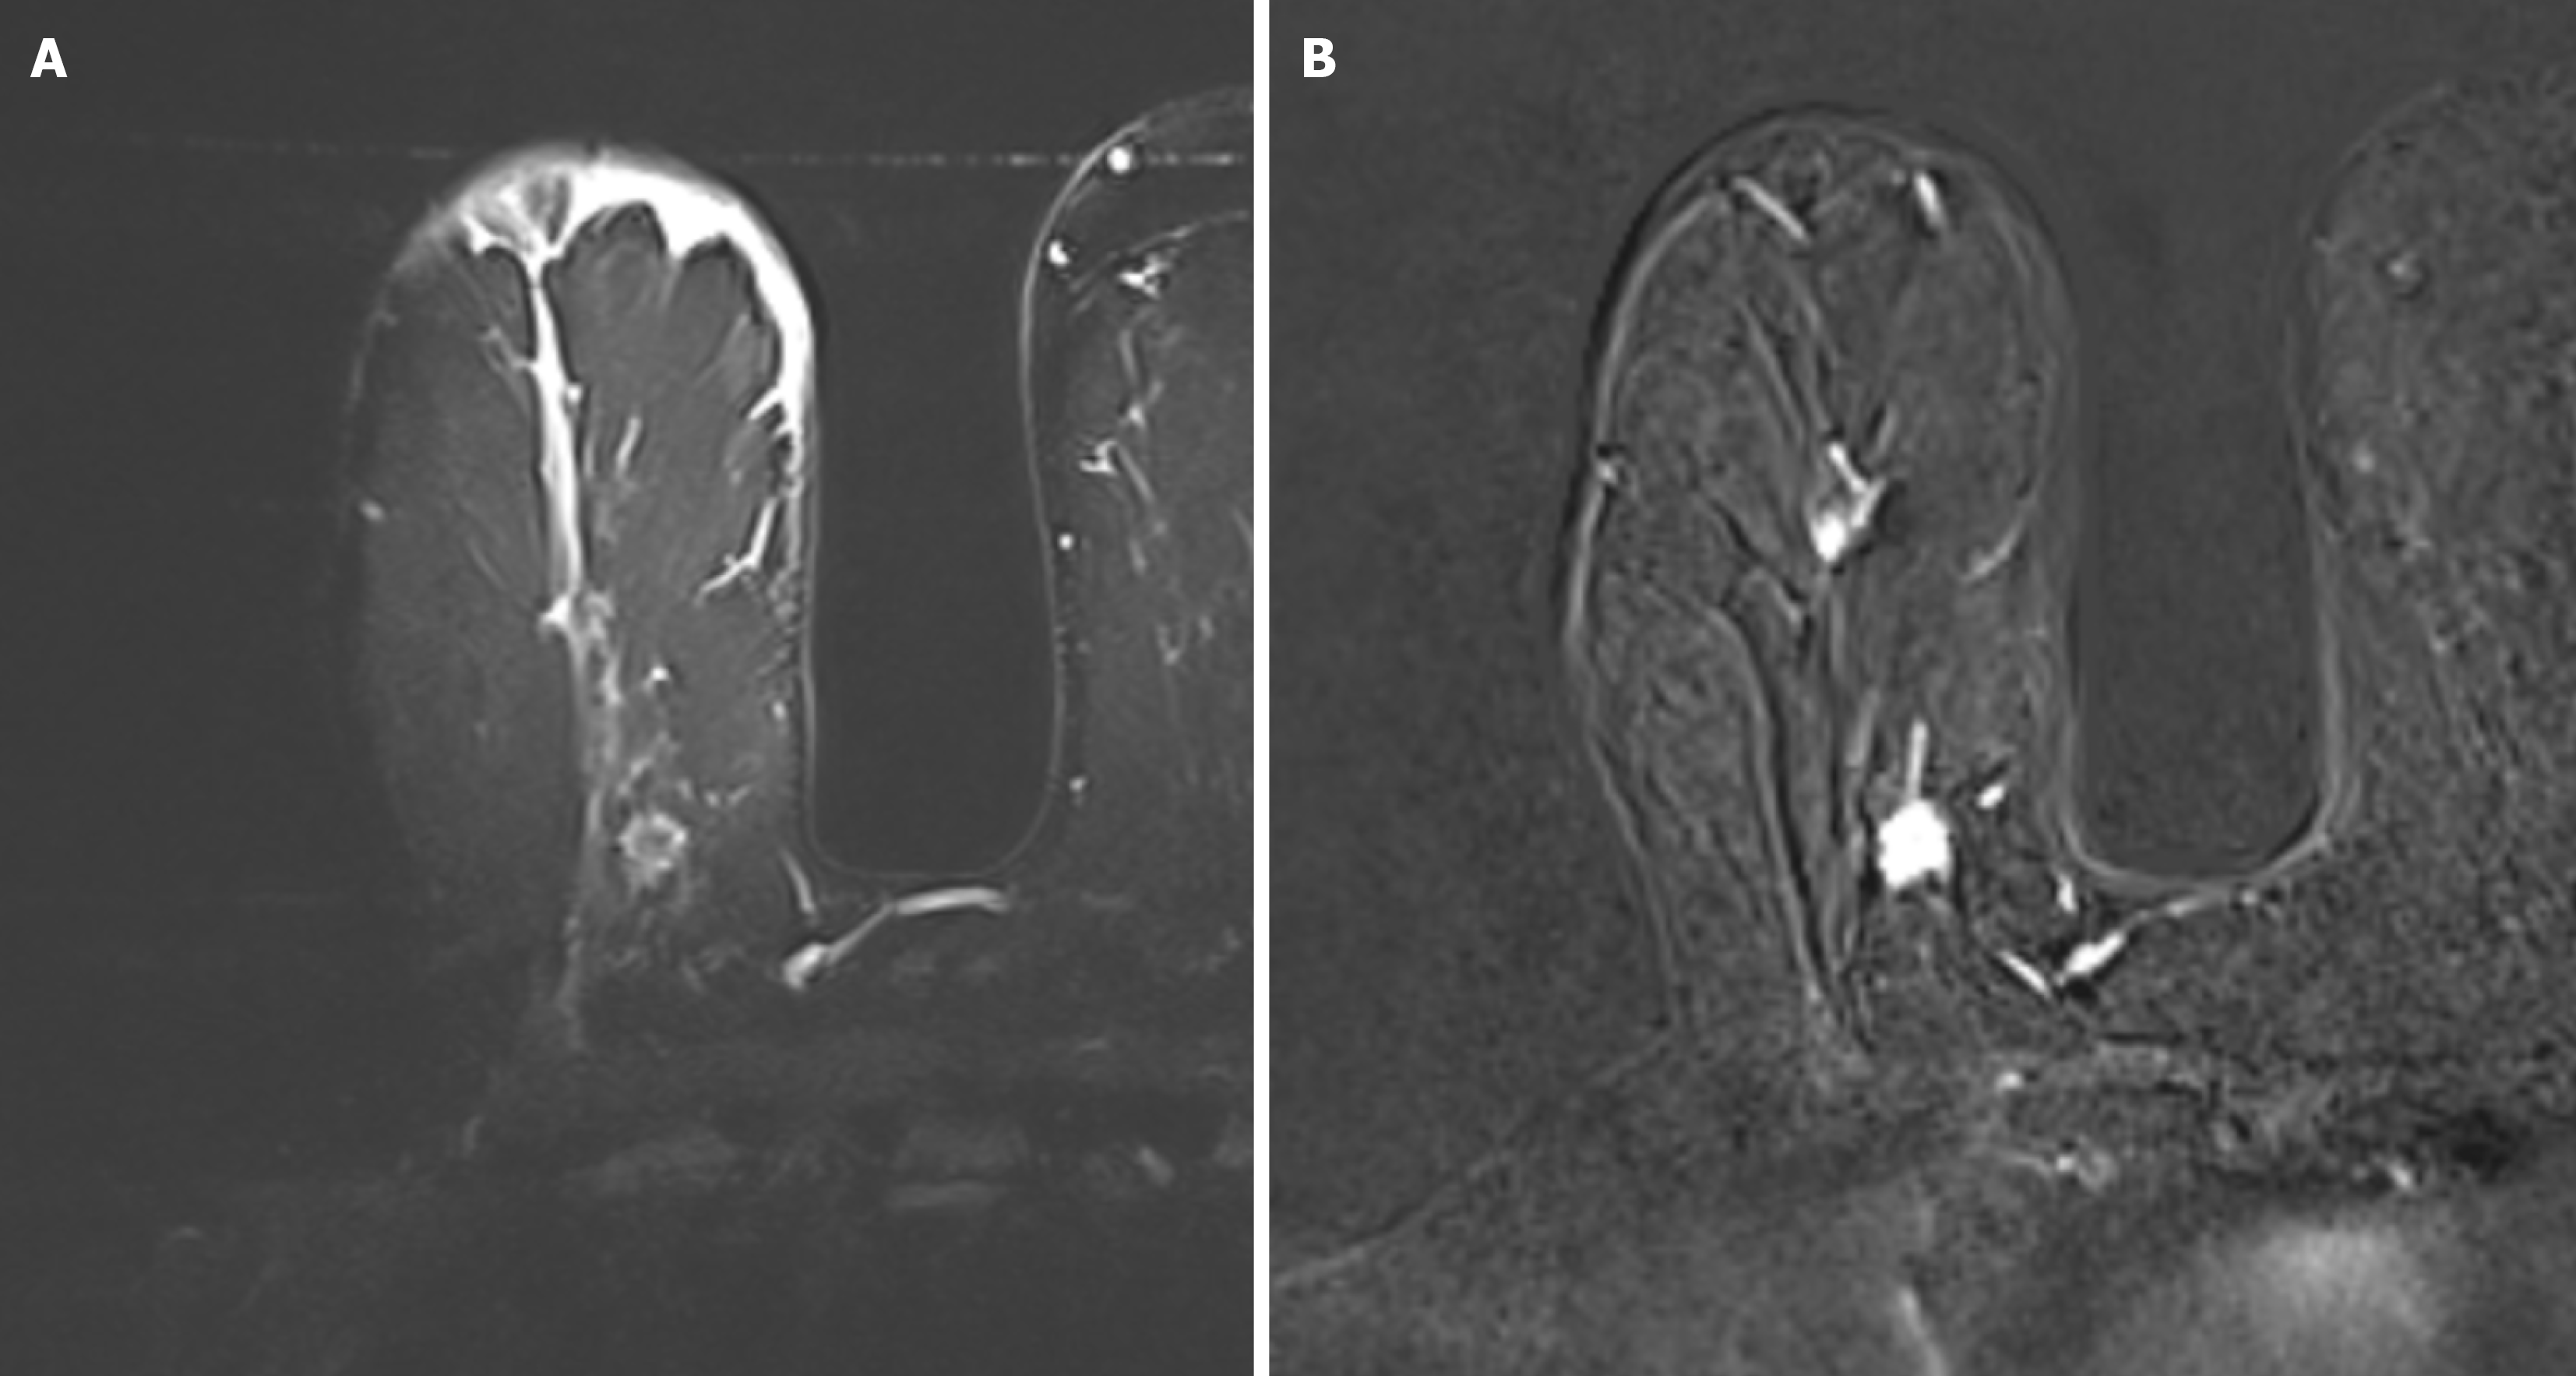

Figure 1 A 71-year-old woman with right breast invasive ductal carcinoma-no special type, luminal A breast cancer.

A: Axial turbo inversion recovery magnitude image shows no edema; B: Axial subtraction images.